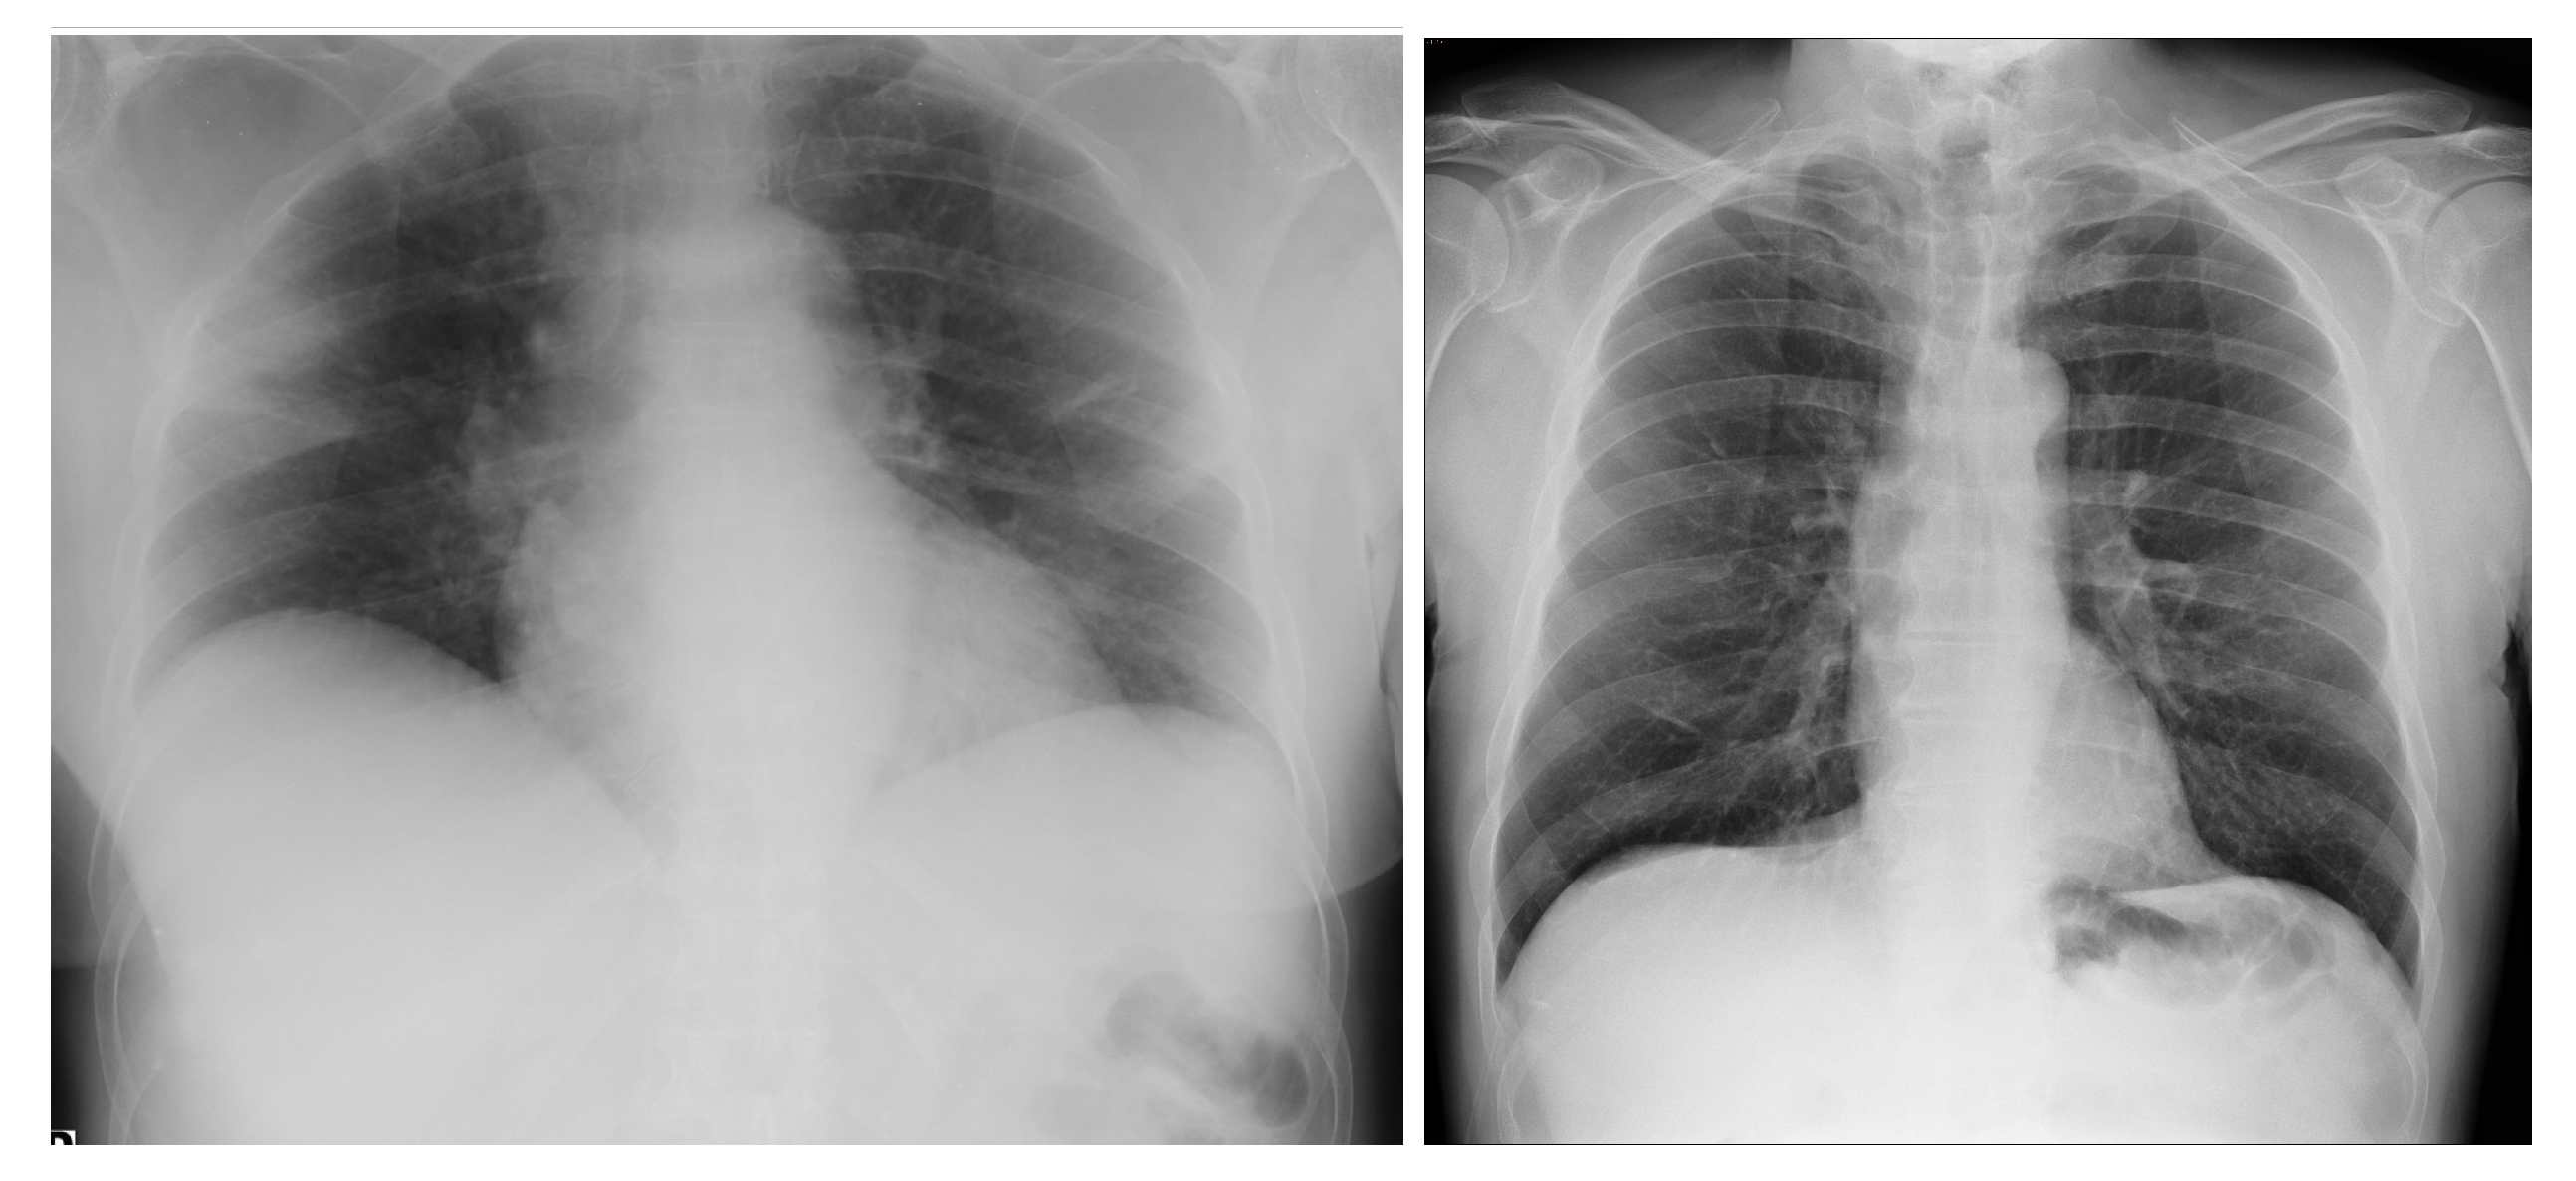

3.4.1. NIH Dataset

3.4.2. COVID-19 Image Data Collection

3.4.3. COVID-19 Radiography

3.4.4. BIMCV COVID19+

3.4.5. Montfort Dataset